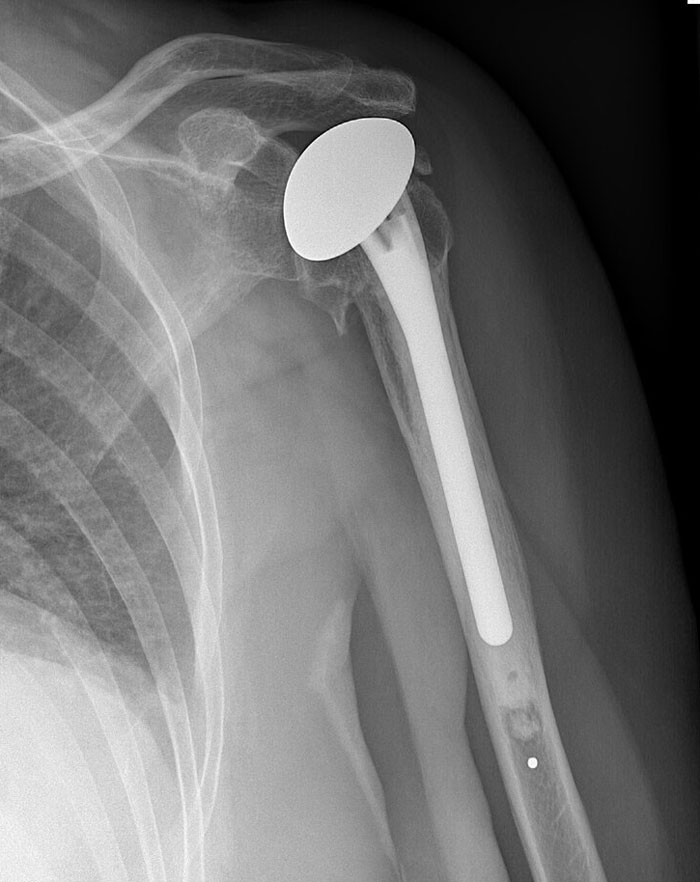

No an autopsy but a human dissection for anatomy class.

We were working on the shoulder area and hit something hard. It wasn’t a bone and made a “clinking” noise.

Turns out our cadaver had a shoulder joint replacement and we were hitting the metal “ball” (for lack of a better term?)

It doesn’t sound like much but it freaked the heck out of a bunch of second year students!!

That was many many years ago and the reason I stopped pursuing medicine!

Image credits: 2018_is_my_year